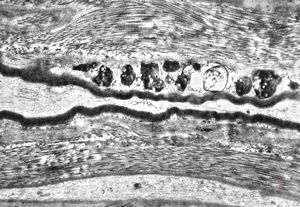

F,31y. | demyelinating hypertrophic neuropathy - n. suralis- bands of Büngner with collagen-filled pockets

M,13y. | - n.suralis - hypertrophic demyelinizing neuropathy

n.suralis - hypertrophic demyelinizing neuropathy

n.suralis - hypertrophic demyelinizing neuropathy